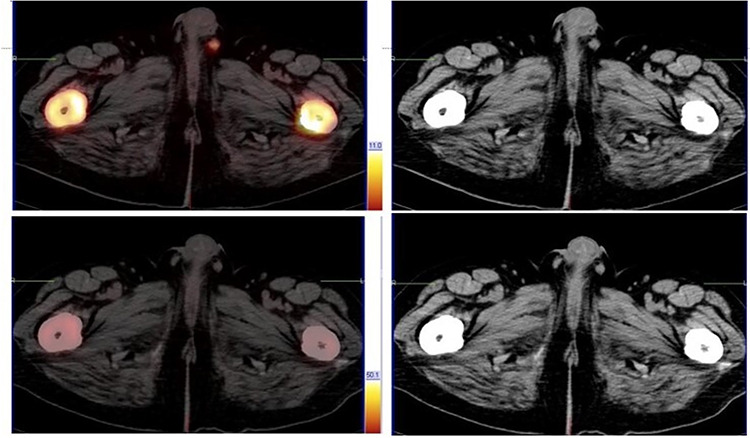

Prostate cancer typically follows a characteristic pattern of metastatic spread to the pelvic lymph nodes and bone. Atypical patterns of metastasis are rare but have been documented. In African men, this disease tends to follow a more aggressive course, with the possibility of an atypical site of metastatic spread. We present a case of a 58-year- old African male with metastatic castrate-resistant prostate cancer who presented with both typical and atypical patterns of metastatic disease detected by a fluorine 18 prostate-specific membrane antigen positron emission tomography/computed tomography scan. This patient also had a good response to radioligand therapy.